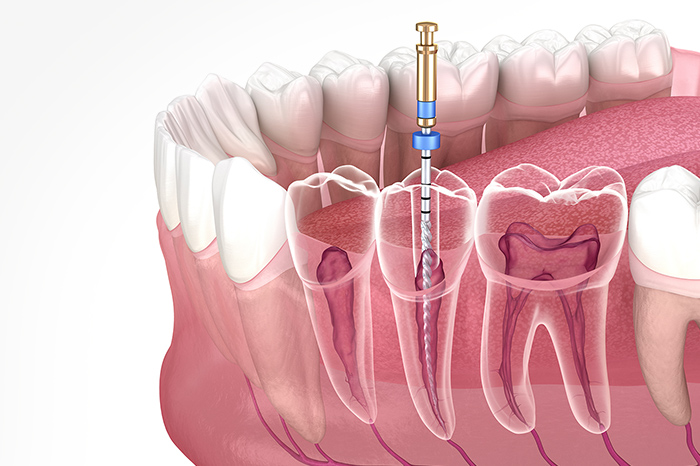

根管治療について

進行してしまったむし歯には

根管治療で歯を残せるよう試みます

根管には神経や血管などの歯髄が詰まっており、むし歯菌に侵されると激しい痛みが生じます。この状態は歯の内側までむし歯が進行しているため、根管治療が必要になります。歯髄を取り除いて根管を洗浄・殺菌し、薬剤を詰めて改善を試みます。根管治療を行うことで、歯を残せる可能性が高まります。